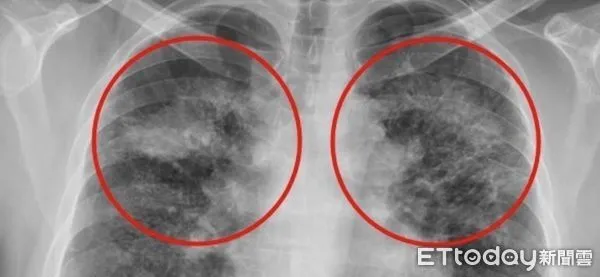

▲矽肺症嚴重時甚至會發展為漸進性大量纖維化,在雙上肺葉形成對稱的腫塊。(圖/慈濟醫學中心提供,下同)

劉迪塑醫師說明,吸入的粉塵大多沉積在上肺葉,因發炎反應和局部纖維化而產生許多間質性結節,嚴重時甚至會發展為漸進性大量纖維化,在雙上肺葉形成對稱的腫塊,臨床上需和惡性腫瘤或結核病的腫塊或結節做鑒別診斷。